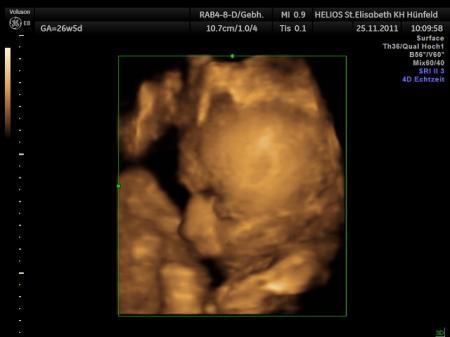

Da kann auch ich mich als Sternchen Mama nur anschießen , liebe Annett wenn du reden bzw. schreiben magst , dann trau dich ruhig . Ich hab ein offenes Ohr. Ps.: welch wundervolles Bild , ein kleiner Engel mit einem grossen Herzen.